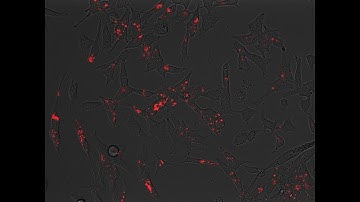

Optimization of ALDEFLUOR™ Protocol